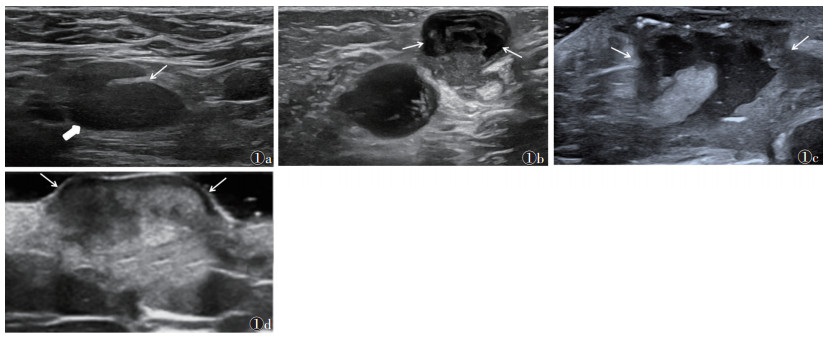

根据BCG-itis的超声表现及病理发展过程[9],将淋巴结分为4种类型:①淋巴结炎型,声像图表现为淋巴结呈长椭圆形或类圆形低回声,边缘清晰,包膜完整,皮质增厚且回声均匀,淋巴结门受挤压但存在(图 1a)。病理表现为淋巴组织增生,实质内见少许不典型结核性肉芽肿形成,肉芽肿中心可见微小的干酪样坏死灶。②干酪坏死型,声像图表现为淋巴结呈椭圆形或类圆形低回声,边缘清晰,包膜完整,内部正常结构大部分消失,回声不均匀,部分呈囊性变,周边组织回声增高(图 1b)。病理表现为正常淋巴结结构消失,存在较多典型结核肉芽肿结构,中央见片状干酪样坏死区,周围软组织水肿。③脓肿窦道型,声像图表现为软组织不规则混合回声包块,边界模糊,包膜不完整,无正常淋巴结结构,内部见斑点状强回声,探头加压内有涌动感,病灶与皮肤真皮层紧贴,部分穿透皮肤层形成窦道(图 1c)。病理表现为典型的结核结节形成,并出现纤维组织增生,脓液中含有大量干酪样物质和肉芽组织。④愈合瘢痕型,声像图表现为真皮层局限性增厚凸出于皮肤表面,呈均质性低回声,与表皮层分界清晰,瘢痕内见彩色多普勒血流信号(图 1d)。病理表现为瘢痕组织内胶原蛋白等基质成分大量沉积,成纤维细胞过度增殖。

| 注:图 1a 为BCG-itis淋巴结炎型声像图,淋巴结皮质增厚(粗箭),淋巴结门受挤压(细箭);图 1b 为BCG-itis干酪坏死型声像图,淋巴结正常结构大部分消失,部分呈囊性变(箭头);图 1c 为BCG-itis脓肿窦道型声像图,无正常淋巴结结构,软组织不规则混合回声(箭头);图 1d 为BCG-itis愈合瘢痕型声像图,真皮层局限性增厚(箭头) 图 1 不同类型卡介苗反应性淋巴结炎(BCG-itis)的声像图 |